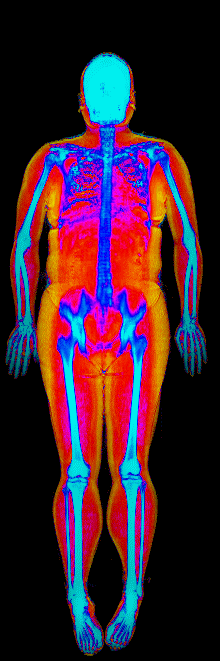

What Muscle Gain Looks Like on a DEXA Scan

Gained 21.7 lb lean · 158 → 184 lb · Age 31

Gained 12.1 lb lean, lost 9.2 lb fat · 188 → 191 lb · Age 27

Gained 9.2 lb lean, lost 6.6 lb fat · 173 → 176 lb · Age 33